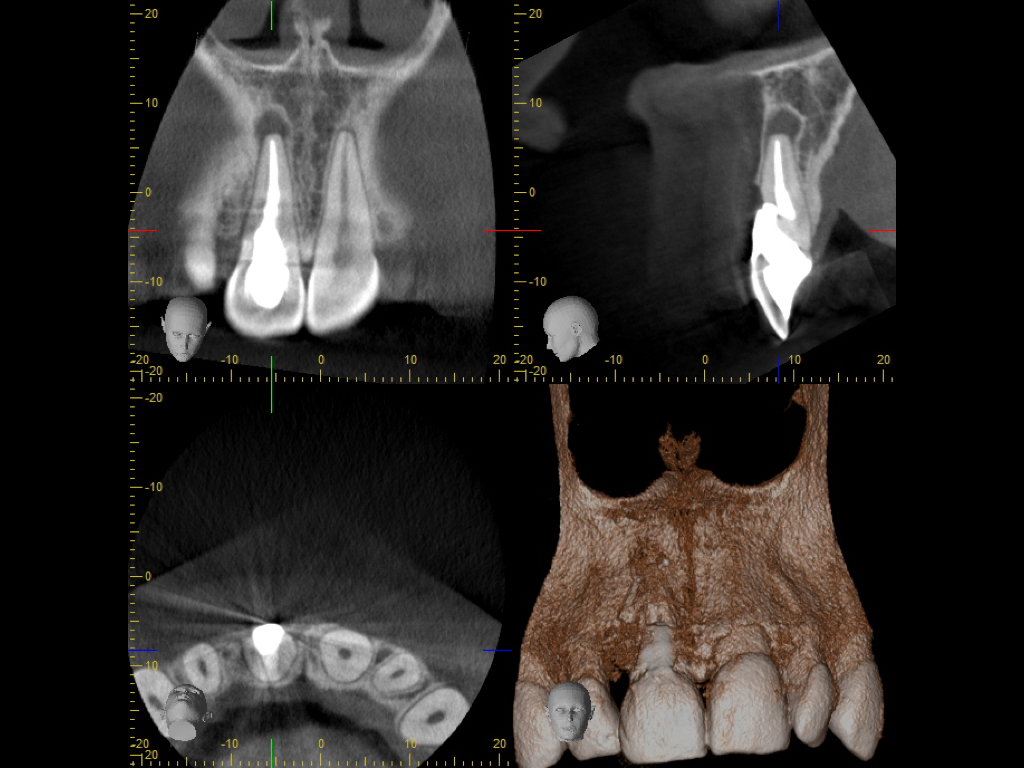

wsi-112016-2-005

Herodontics (1)